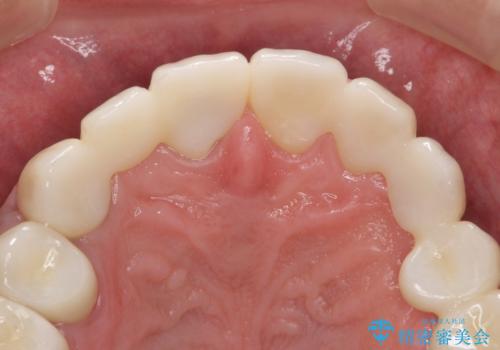

オールセラミッククラウン ブリッジによる欠損歯の補綴

インプラントは希望されなかったため、左側は1番から7番のロングスパンブリッジによる補綴を行いました。

今回用いたオールセラミッククラウンは、ジルコニアフレームという白い素材の上にセラミックを盛っているため審美性が非常に高いのが特徴です。

またジルコニアは人工ダイヤモンドの材料にも使われているほど高い強度を持っており、そのためオールセラミッククラウンは審美性だけでなく、奥歯やブリッジの補綴も可能とするクラウンです。